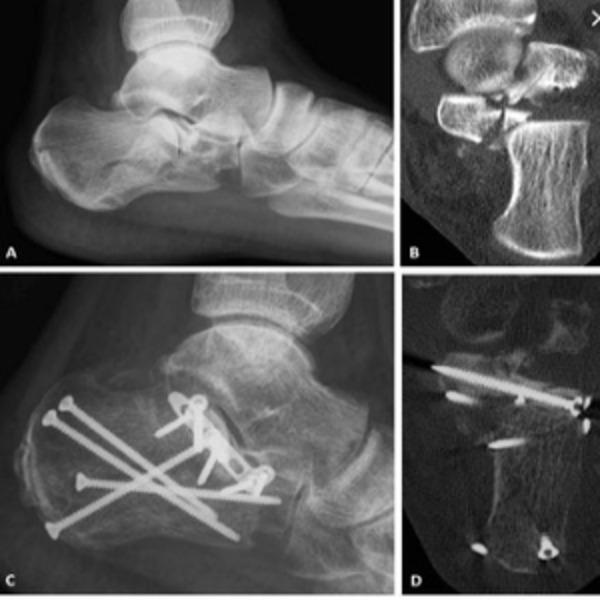

Best Foot and Ankle Surgeon in Nagpur – Expert Care for Foot Health

View DetailsBest Foot and Ankle Surgeon in Nagpur – SUYOG HOSPITAL NAGPUR